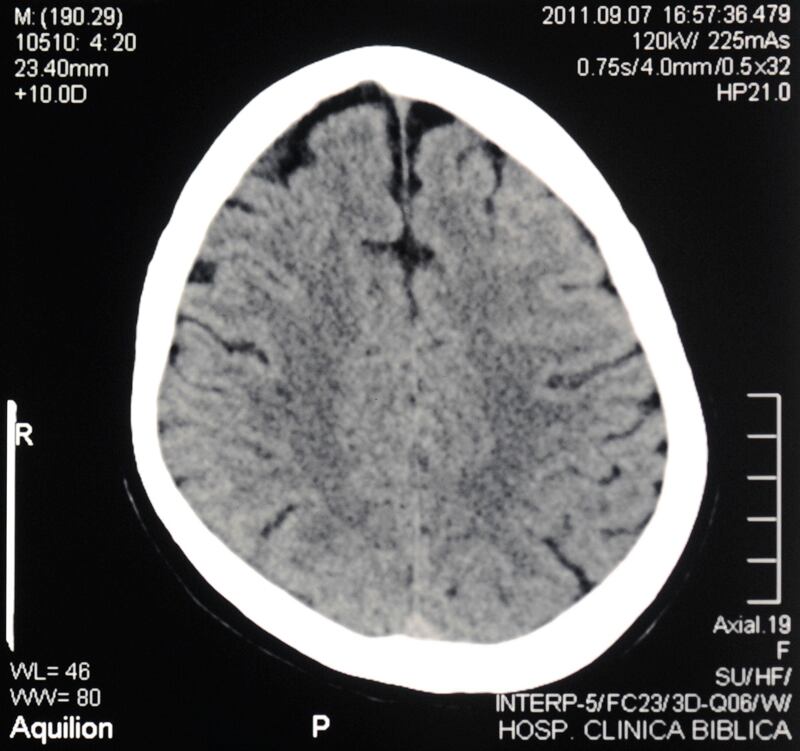

Para el médico Franz Chaves Sell , especialista en neurología de la Clínica Bíblica, es infinitesimal lo que conocemos del cerebro hasta el día de hoy. Como factores que han dificultado esa mayor aproximación, cita sus complejas redes neuronales y el hecho de que las funciones cerebrales no están localizadas en un sitio en particular, sino que son producto de las activaciones de ese entramado de redes.

Las investigaciones clínicas buscan tratamientos para la enfermedad de Parkinson , el alzhéimer, las epilepsias, los tumores cerebrales y las enfermedades cerebrovasculares. Se busca identificar los factores de riesgo que permitan prevenir y no solo curar.

O los avances de la neuronavegación (técnica de triangulación para encontrar con más precisión lesiones intracraneanas o tumores), la neuroendoscopía (tratamiento de patologías cerebrales a través de pequeños orificios en el cráneo), y la cirugía de epilepsia...